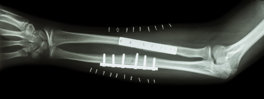

Our client was a passenger in a car which crashed into another vehicle resulting in a serious injury to his left leg. He had to have several operations over several years including amputation of his left leg below the knee. As a result of the car accident he couldn’t return to his job which required travelling.